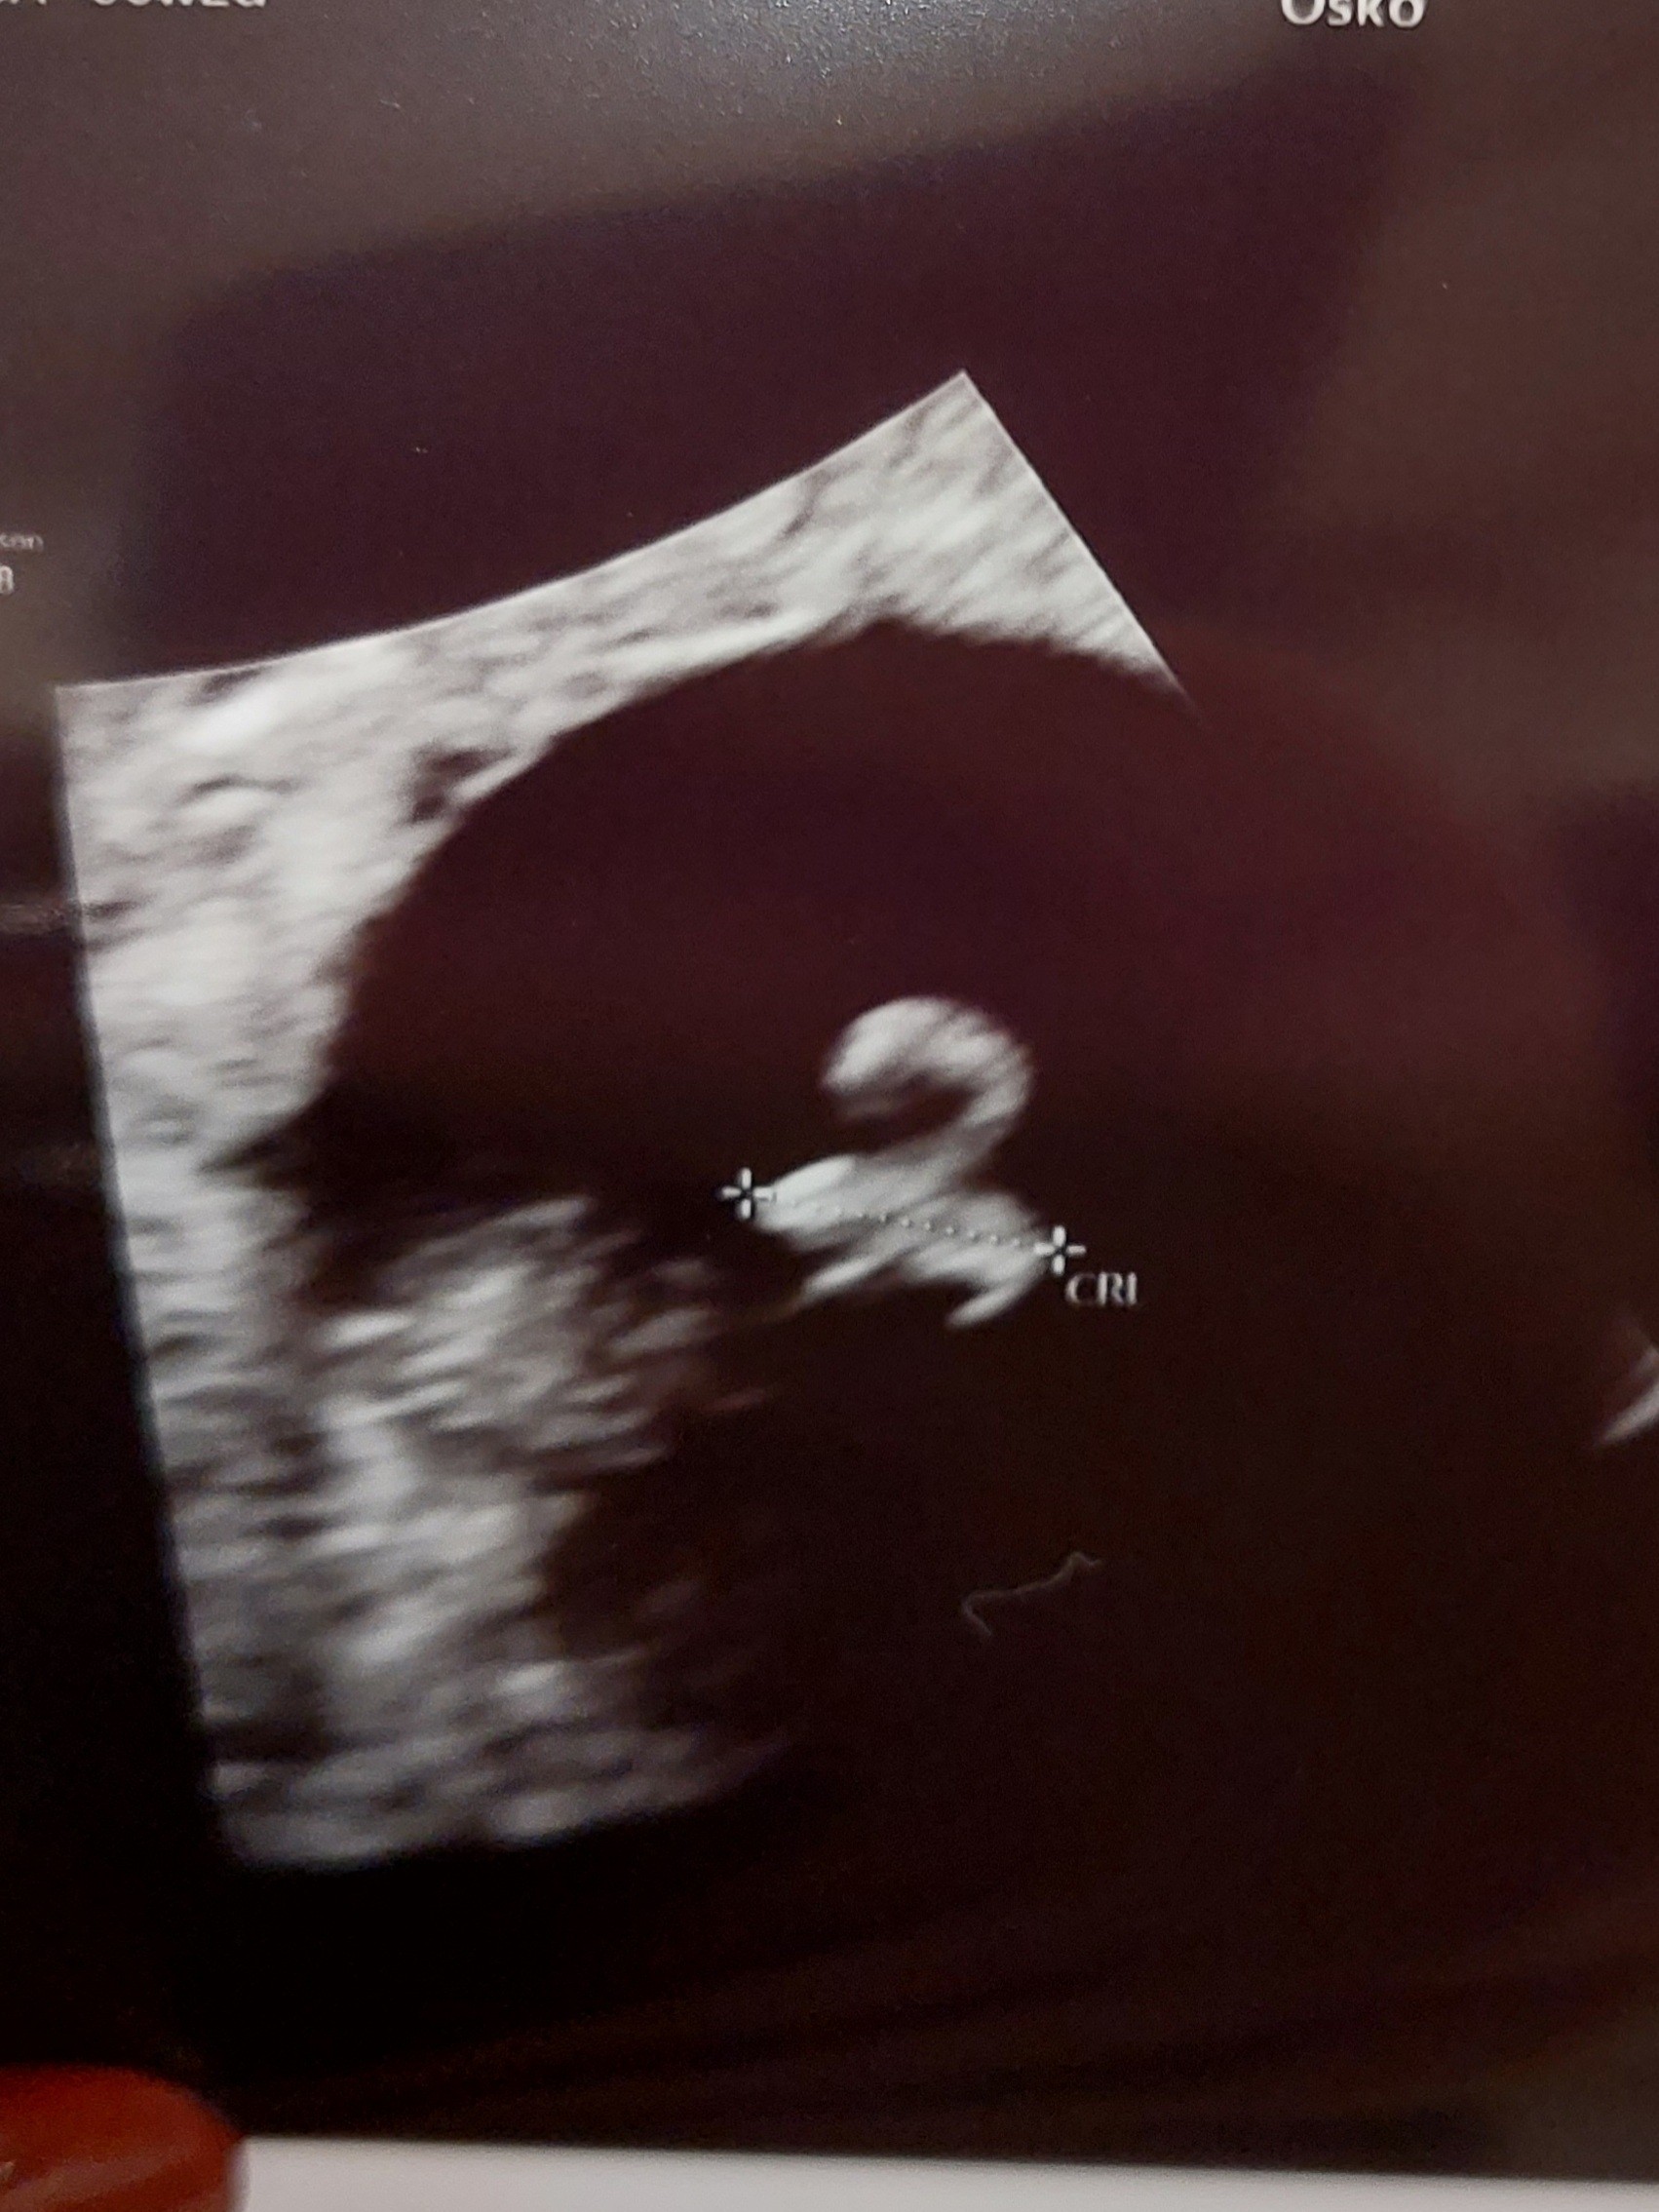

ogólnie najważniejsza informacja jest taka, że zobaczyła pęcherzyk i zarodek. Poza tym kobieta nie udzieliła mi żadnej konkretnej informacji. Jestem wściekła wręcz.

Ja po wizycie u gin. Widać maciupeńką kropeczkę, dodatkowo solidny torbiel :/. Z racji pierwszego poronienia dostałam progesteron na podtrzymanie. Wizyta kontrolna za 2 tyg. Będą to najdłuższe 2 tyg w życiu, by móc zobaczyć fasolkę